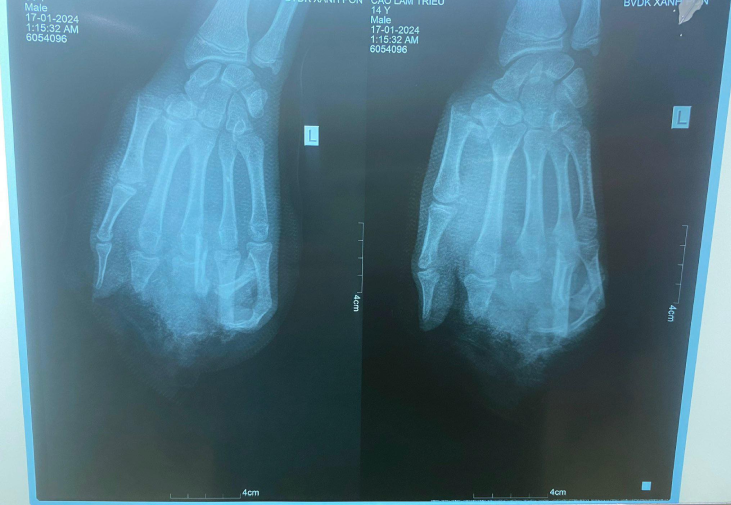

Ngày 19/1, tin từ Bệnh viện Xanh pôn (Hà Nội) cho biết, bệnh viện vừa có tiếp nhận 1 bệnh nhân nam 14 tuổi, tai nạn sinh hoạt do nổ bình gas mini khi đang ăn lẩu. C.T.L., (14, tuổi, trú tại Hải Dương), được gia đình đưa cấp cứu trong tình trạng tình trạng dập nát bàn tay trái, gãy xương bàn ngón I, đầu ngón I, V còn hồng.

| Hình ảnh phim chụp X-quang của bệnh nhân. (Ảnh: BVCC) |

Với tổn thương này, bác sĩ đánh giá vấn đề chức năng bàn tay của bệnh nhân sẽ bị giảm đi rất nhiều, ảnh hưởng lớn đến học tập, sinh hoạt và lao động sau này, đặc biệt còn ảnh hưởng đến tâm lý.